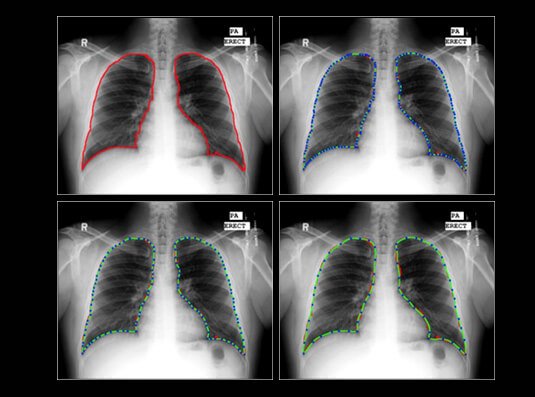

The medical field has great potential for the implementation of artificial intelligence. In this post, we look at how AI evidently surpasses humans in diagnosing patients using x-rays. As AI becomes more adapted and smarter in image recognition, the chances of an AI correctly diagnosing a patient with bronchitis are no longer just a concept.Continue reading “AI in Radiology”